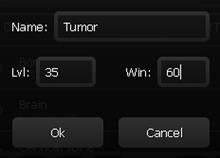

11.1.2. Annotations-Menü

Wenn eine Notiz oder eine Messung erstellt wurde erscheint im Werkzeugmenü folgender Button (siehe Liste der Annotationen).

-

Öffnet das „Liste der Annotationen“-Fenster

-

Einfaches Anklicken wählt die Annotation aus und springt im Betrachtungsfenster direkt zu dieser. Langes Halten eines Eintrags ruft das Untermenü auf (Punkt 2,3).

-

Löschen der ausgewählten Annotation.

-

Name der ausgewählten Annotation bearbeiten.